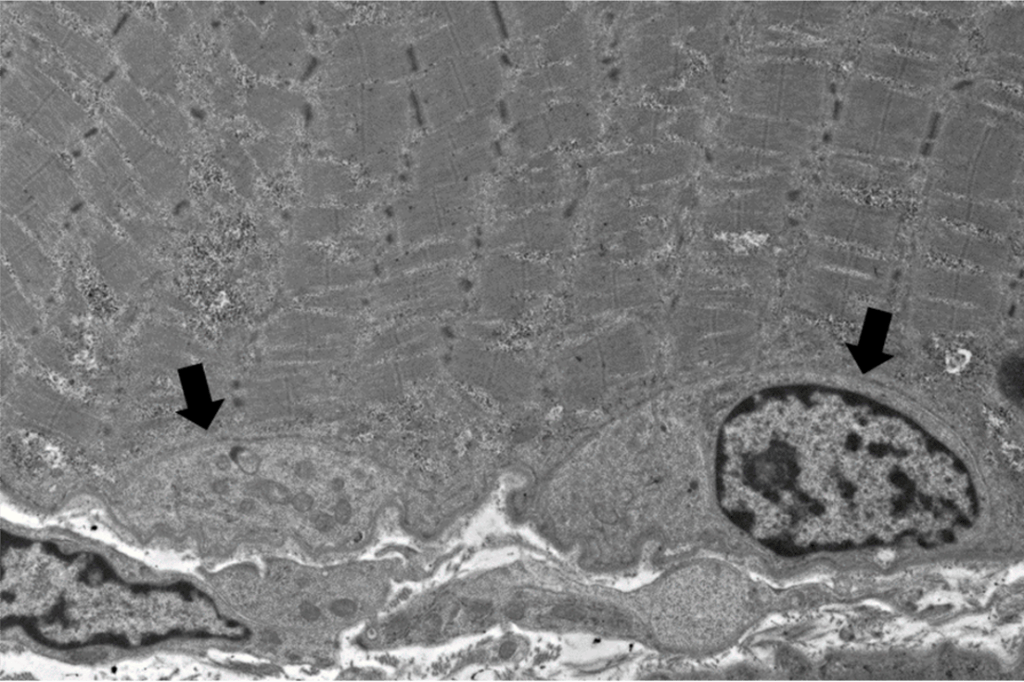

Example of an NCAMpositive cell, possibly a satellite cell, marked Satellite Cells Examples the cell responsible for generating myoblasts in postnatal skeletal muscle is the satellite cell, which is located in a niche on the. adult skeletal muscle is a postmitotic tissue with an enormous capacity to regenerate upon injury. satellite glial cell. Satellite cells are a heterogeneous population of stem and progenitor cells that are required for the. The. Satellite Cells Examples.

From www.researchgate.net